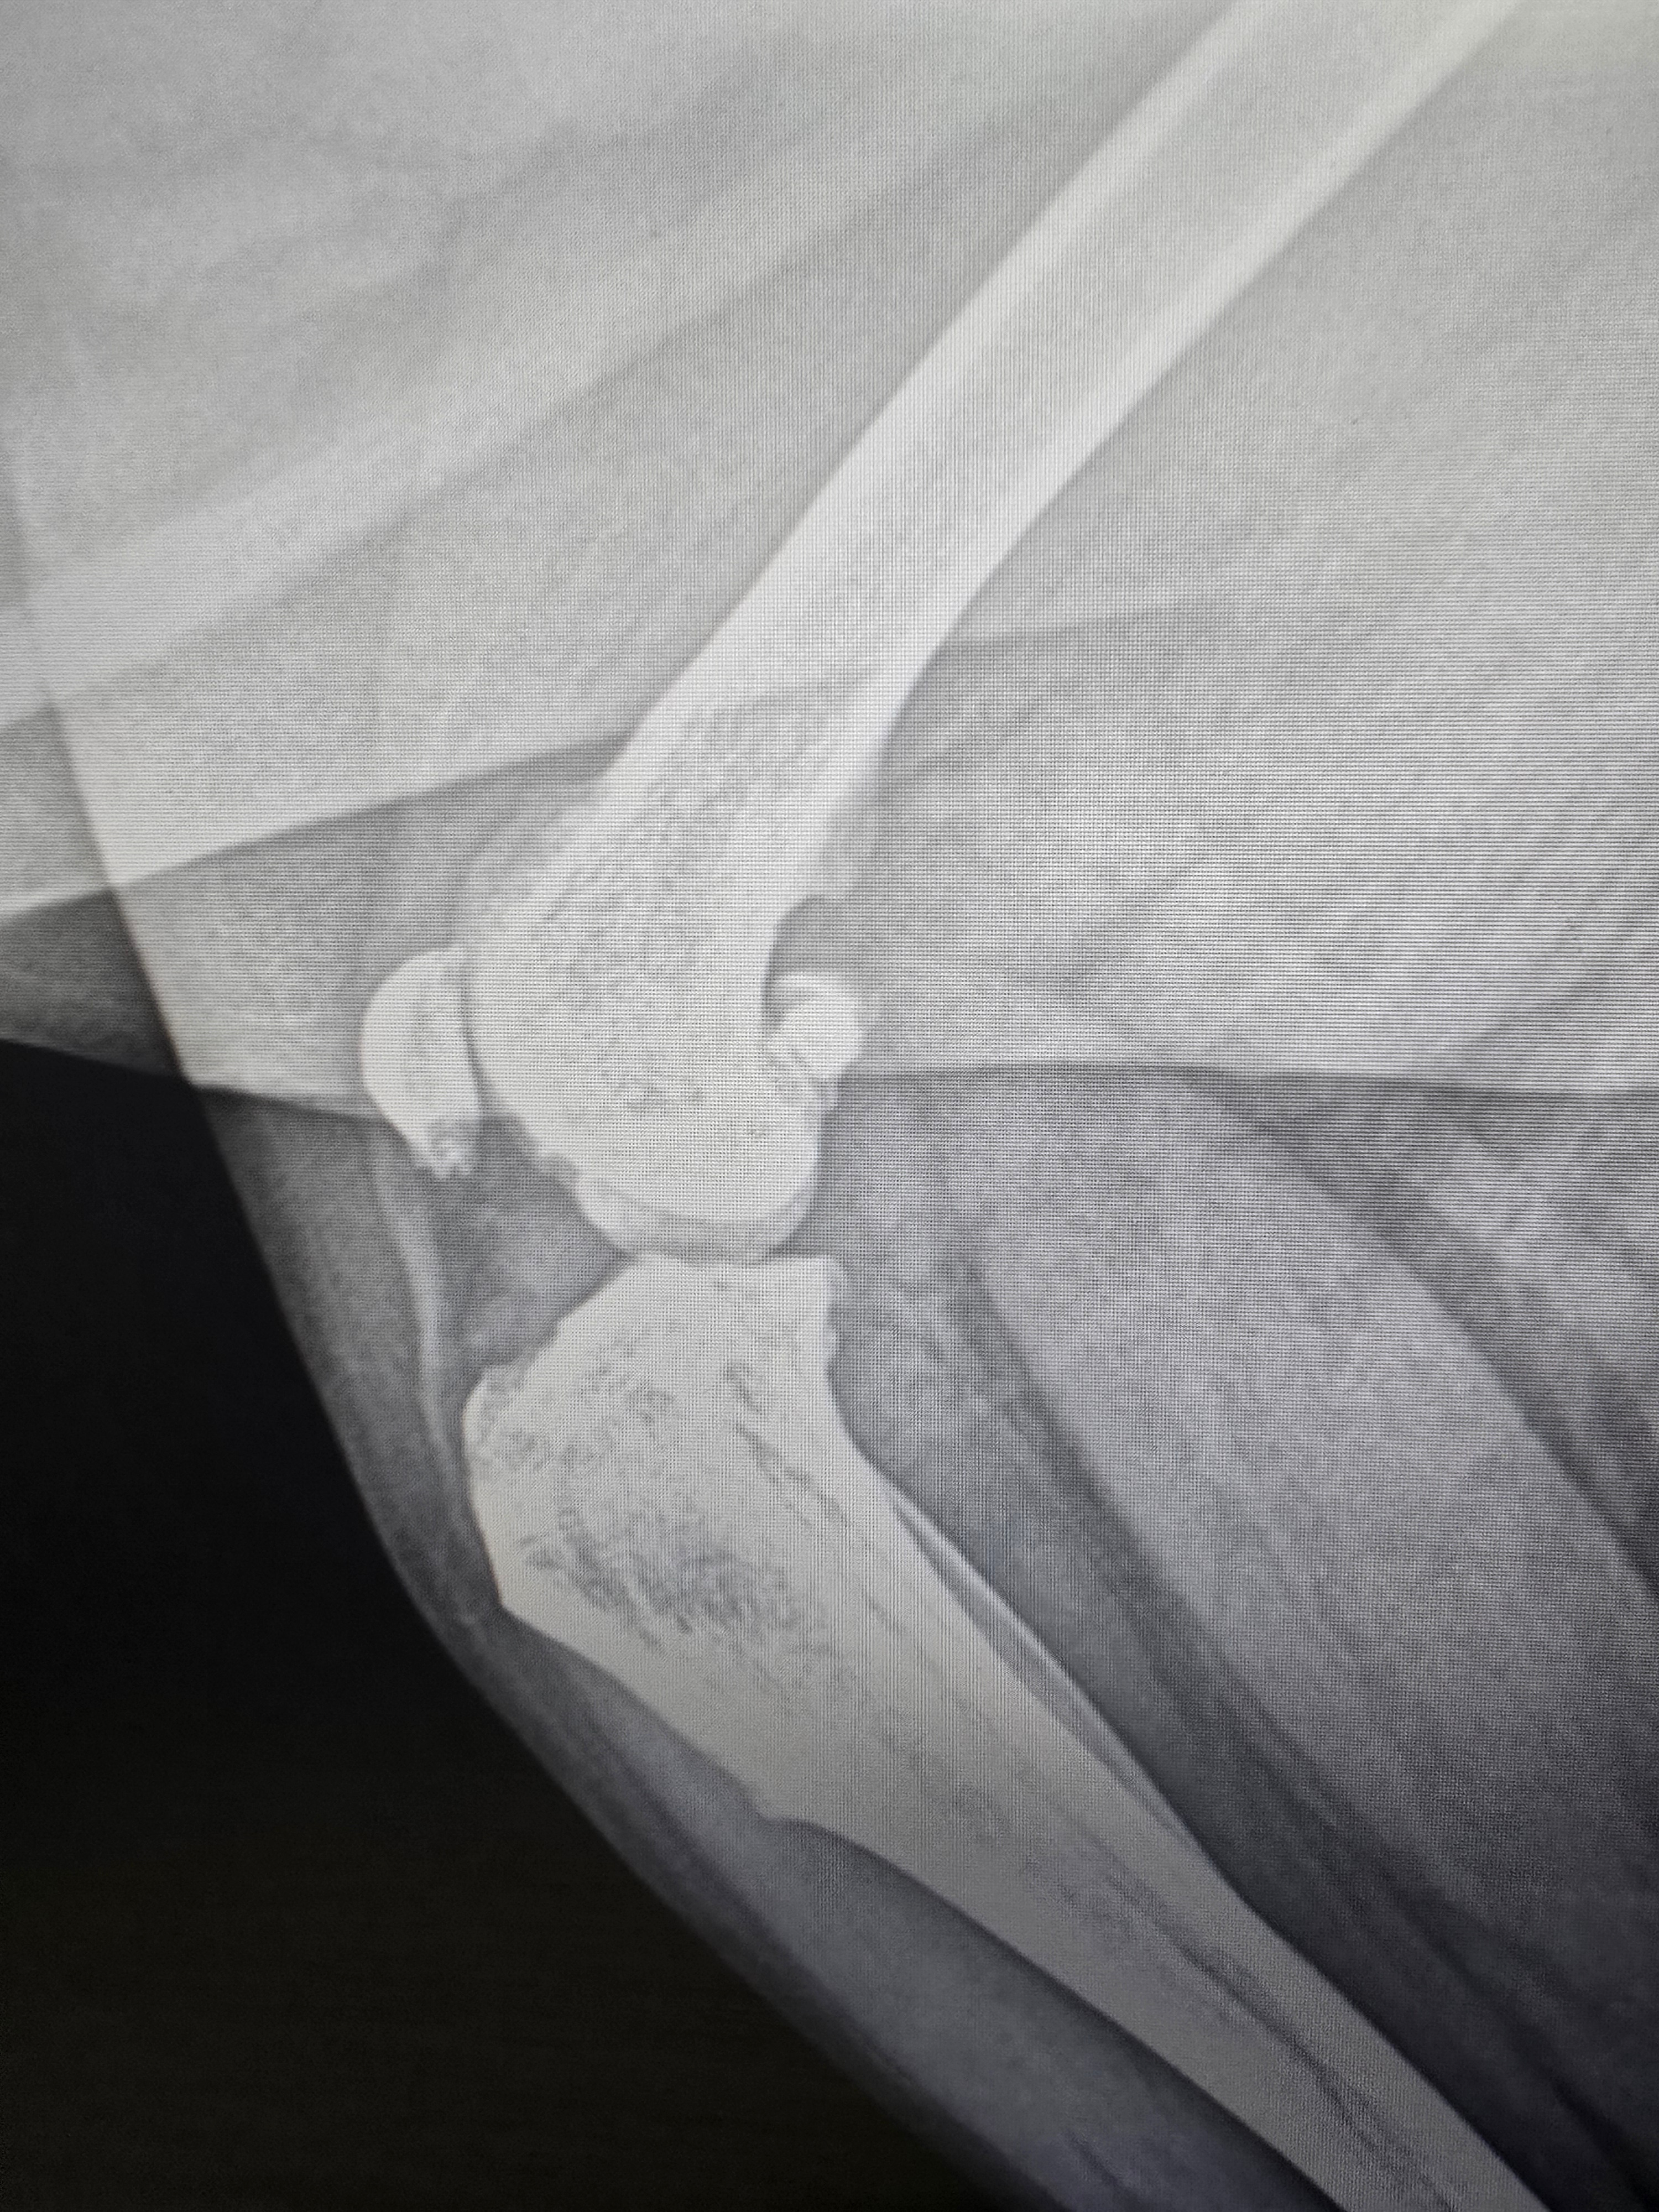

A few weeks ago, she tore her cruciate ligament while trying to hop onto the couch.

We were able to get her into the vet's office and get x-rays of her knee. The vet offered to send the work to a vet surgeon who lives 4 hours away, and we can't do that. Thankfully, another vet office up here, Blue Ridge Pet Clinic, said they could do the surgery. We have set up an appointment for the 7th to talk about what will happen, and we already know it will be a bit of money for the surgery.